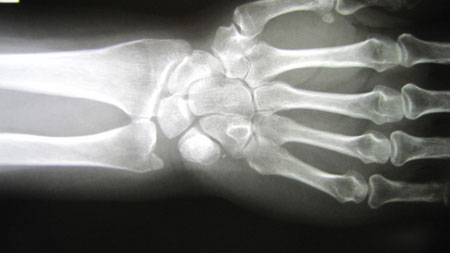

○ 学生アスリート 手首の骨折

手を突くとおおよそ骨折するところが決まってきます。

橈骨遠位端骨折と言って手関節のすぐ上のところが骨折します。みなさんは骨折と診断されると痛みは骨だけからくると思いがちですが、実は手を突いた時に手関節の捻挫も起こしています。靱帯や軟部組織が壊され、さらに力が骨に及んで骨折をおこします。今回は確かに骨の圧痛とレントゲンは陽性でしたが転位はなく、どちらかと言えば捻挫による痛みが強く思われたので手首だけを簡単な固定にしました。また取り外しできるように工夫しました。

通常病院ですと肘から指まで一ヶ月固定するでしょう。

この程度の固定ですとストレスもなく当然お風呂は固定を外し入ってもらいました。一ヶ月しないで復帰しました。